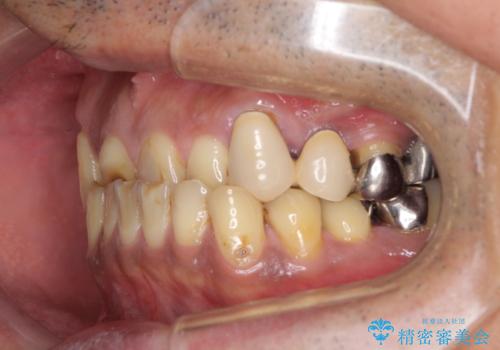

- すり減った前歯や奥歯の銀歯を気にして来院された患者様です。

骨格的な反対咬合により上顎前歯の先端が顕著にすり減っている状態でした。

奥歯の欠損が散見されており、銀歯の装着されている歯も多いため、ワイヤー矯正にて歯列を調整し、その後オールセラミッククラウンにて補綴治療を行うこととしました。

反対咬合改善には奥歯の咬み合わせをしっかりと改善させることが必要となりますが、奥歯に欠損が多いため、矯正治療が難航することが予想されます。